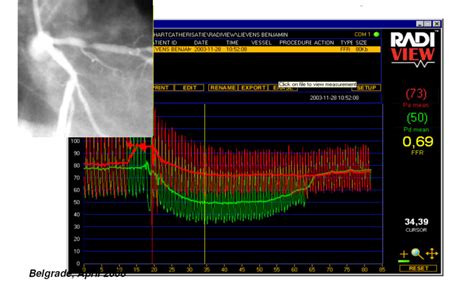

Fractional Flow Reserve (FFR) is a minimally invasive diagnostic technique used during coronary angiography to assess the physiological significance of coronary artery stenoses (narrowings). It measures the pressure difference across a stenosis to determine whether it is causing a significant reduction in blood flow to the heart muscle. This information helps cardiologists decide whether to perform revascularization (e.g., angioplasty or bypass surgery) to improve blood flow or to manage the patient with medical therapy alone. FFR is based on the principle that a stenosis that significantly reduces blood flow will have a lower pressure distal (downstream) to the narrowing compared to the pressure proximal (upstream) to the narrowing. The FFR value is calculated as the ratio of the distal coronary pressure to the proximal coronary pressure during maximal hyperemia (increased blood flow). An FFR value of 0.80 or less indicates that the stenosis is causing a significant reduction in blood flow and that revascularization is likely to be beneficial. Conversely, an FFR value above 0.80 suggests that the stenosis is not significantly affecting blood flow and that medical therapy may be sufficient. FFR has been shown to improve clinical outcomes and reduce the need for unnecessary revascularization procedures compared to angiography alone. It is now a standard of care in many cardiology practices for the evaluation of coronary artery disease. By providing objective, physiological data, FFR helps cardiologists make informed decisions about the best course of treatment for their patients, ultimately improving their quality of life and reducing the risk of adverse cardiac events.

4. Calculating the FFR: During hyperemia, the pressure sensor measures the pressure on both sides of the blockage. The FFR is calculated as the ratio of the pressure after the blockage to the pressure before the blockage. So, it’s a simple division: Pressure Downstream / Pressure Upstream.

5. Interpreting the Results: This is where the magic happens. The FFR value is a number between 0 and 1. Here’s what it means:

• FFR > 0.80: This usually means the blockage isn’t significantly affecting blood flow. You might not need a stent or angioplasty, and medication might be enough.

• FFR ≤ 0.80: This suggests the blockage is significantly reducing blood flow. In this case, a procedure to open the artery, like angioplasty with stenting, is often recommended to improve blood flow and reduce symptoms.